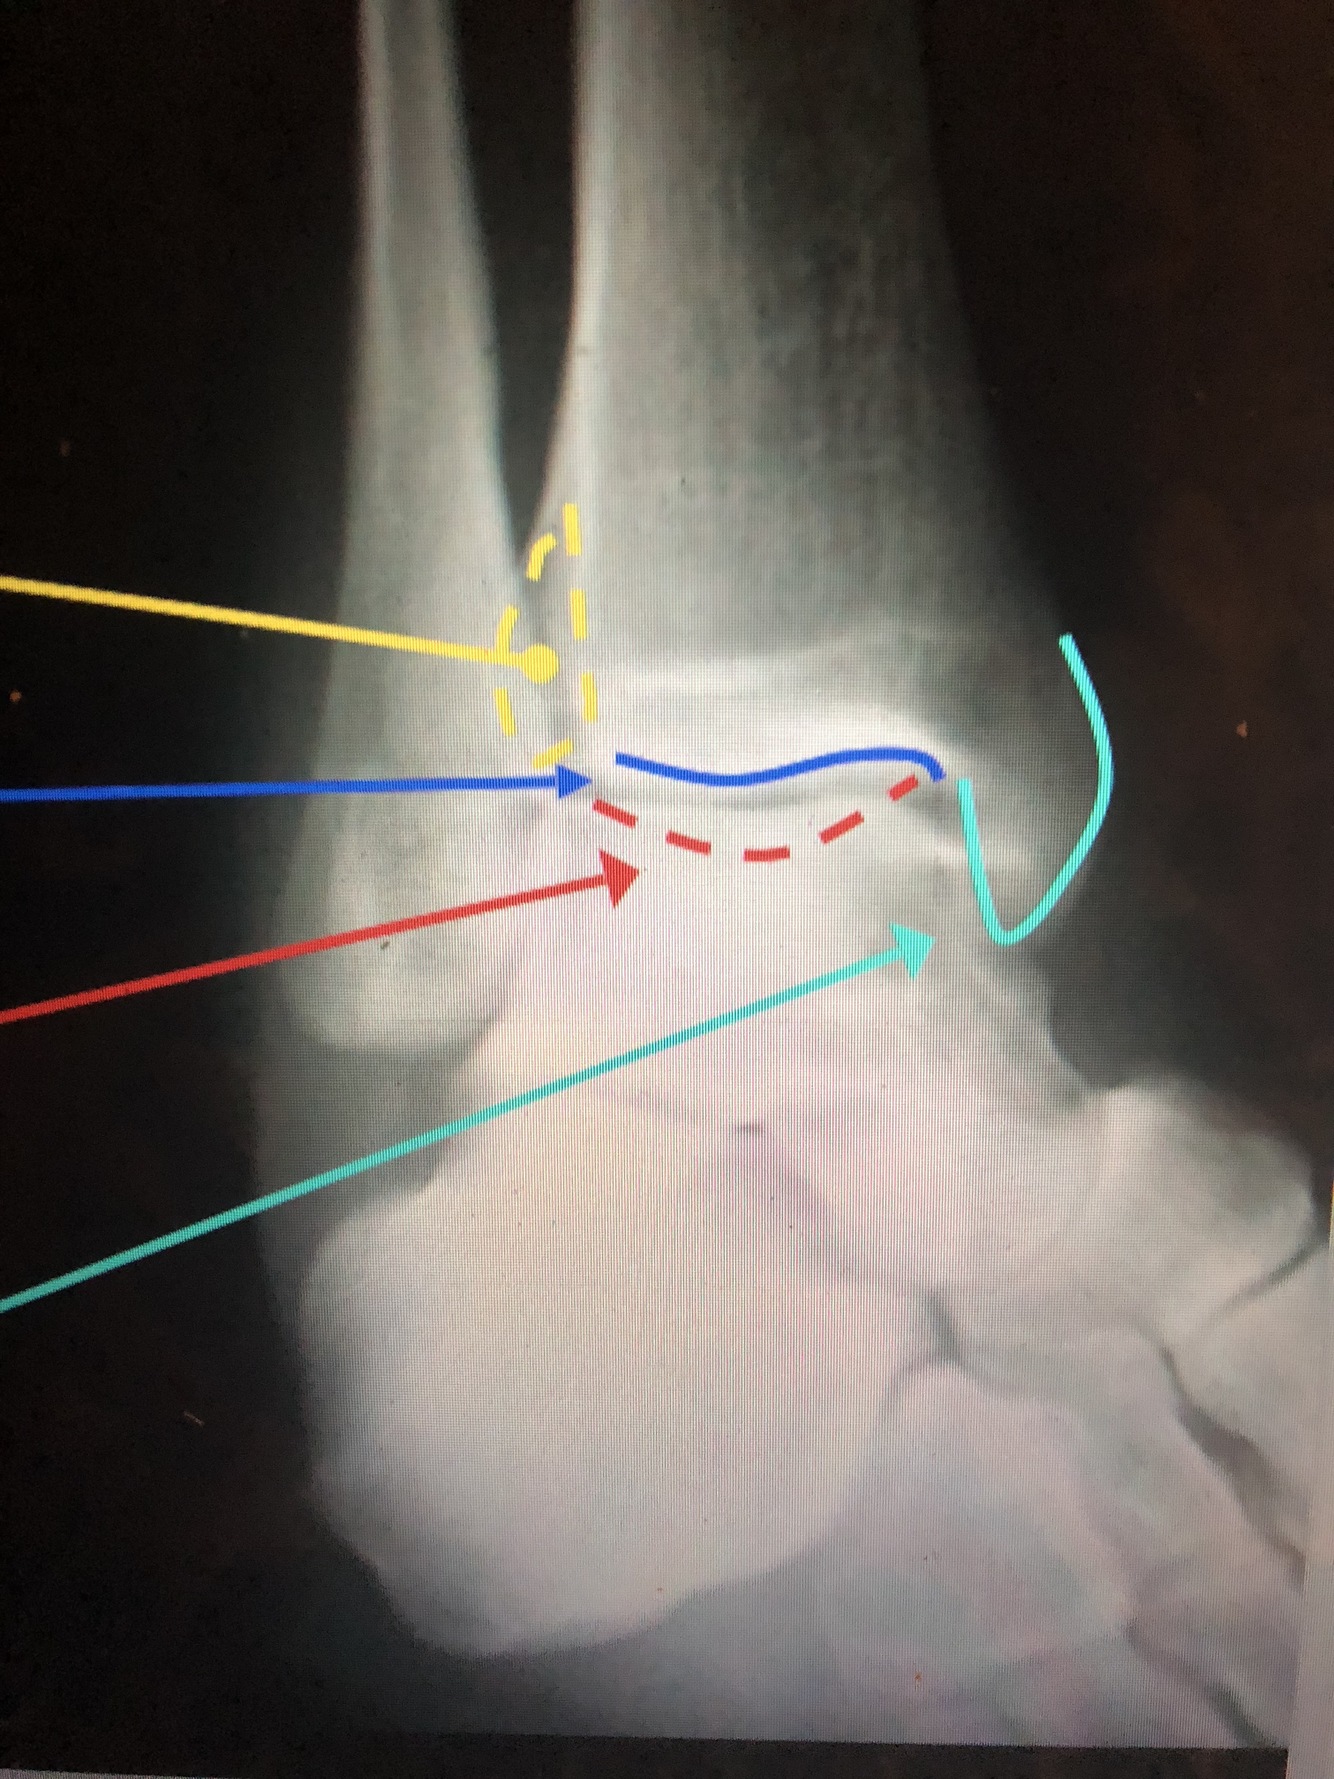

What is the dark blue line?

Lateral margin of the Tibia

What is the red line?

Plafond

What is the light blue line?

Medial Malleolus

Interosseous Crest of the distal tibia

What is the light blue dotted line?

Fibular Notch

What is the red dotted line?

Posterior Malleolus